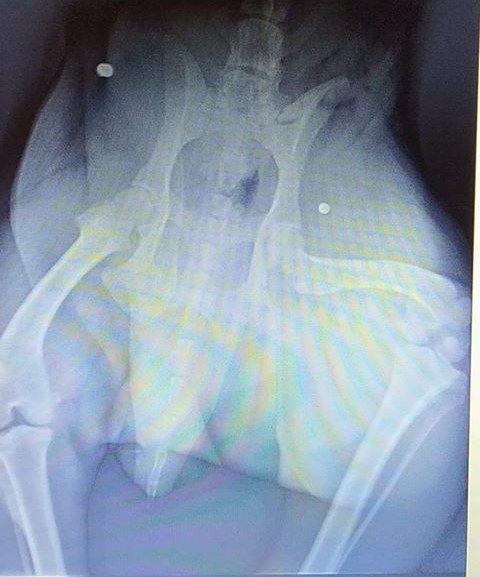

Nasz pies ma wbite 2 śruty. Pies nie kwalifikuje się do operacji. Bardzo cierpi. Ma założony cewnik, jest napuchnięty w tylnej części ciała ma uszkodzone nerwy z tego względu nie może chodzić. Prawdopodobnie zostanie uśpiony. Dwóch lekarzy powiedziało, że nie podejmie się operacji – opisuje zdarzenie pan Paweł i prosi o informację, czy już ktoś w regionie był w podobnej sytuacji.

Jak mówi nam Czytelnik, który przesłał fotografie prześwietlenia swojego psa, na zdjęciu widać dwa rodzaje śrutu.

Nie trzeba być balistykiem żeby dopatrzyć się, że pies został postrzelony od góry. Wydaje mi się, że z dwóch wiatrówek – mówi nam właściciel psa.